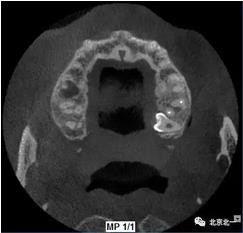

圖三:橫斷面可見智齒水平橫向腭側(cè)。完全骨埋伏。